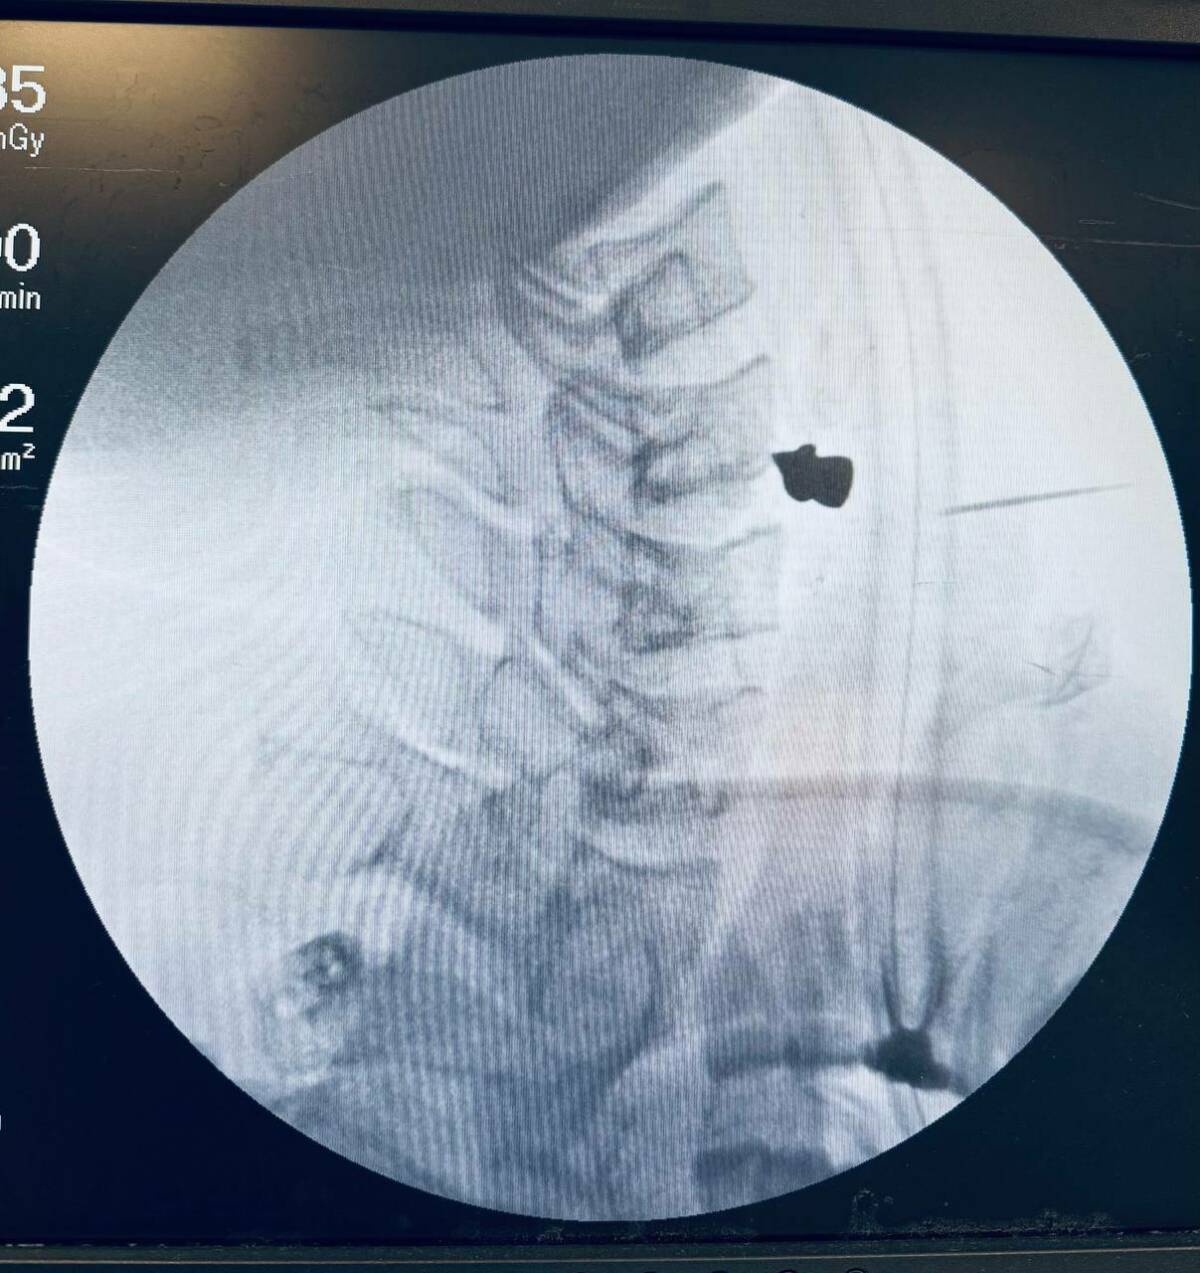

Фото: Пресс-служба РКБ

Пулю, чудом не задевшую ни одну артерию, извлекли из шеи пациента в Республиканской клинической больнице Татарстана. Об этом сообщила пресс-служба клиники.

25-летний житель Зеленодолького района случайно выстрелил в себя, неосторожно обращаясь с пневматическим ружьем. Парень рассказал, что разбирал оружие и не заметил, как сработал механизм, – услышал выстрел и почувствовал, что из шеи полилась кровь. Молодой человек оказался в Зеленодольской ЦРБ, откуда его перевели в РКБ.

Мужчине было трудно глотать и говорить. К счастью, ни артерии, ни трахея, ни пищевод задеты не были – пуля прошла через шею и остановилась в позвоночнике. Заведующий ЛОР-отделением Марат Гилялов и заведующий отделением нейрохирургии №2 Георгий Майков аккуратно извлекли пулю и зашили рану – вся операция заняла 20 минут.